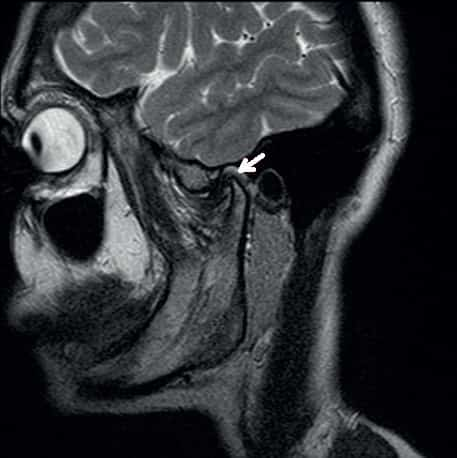

Челюстно лицевое узи

Челюстно лицевое узи 108 фотографий